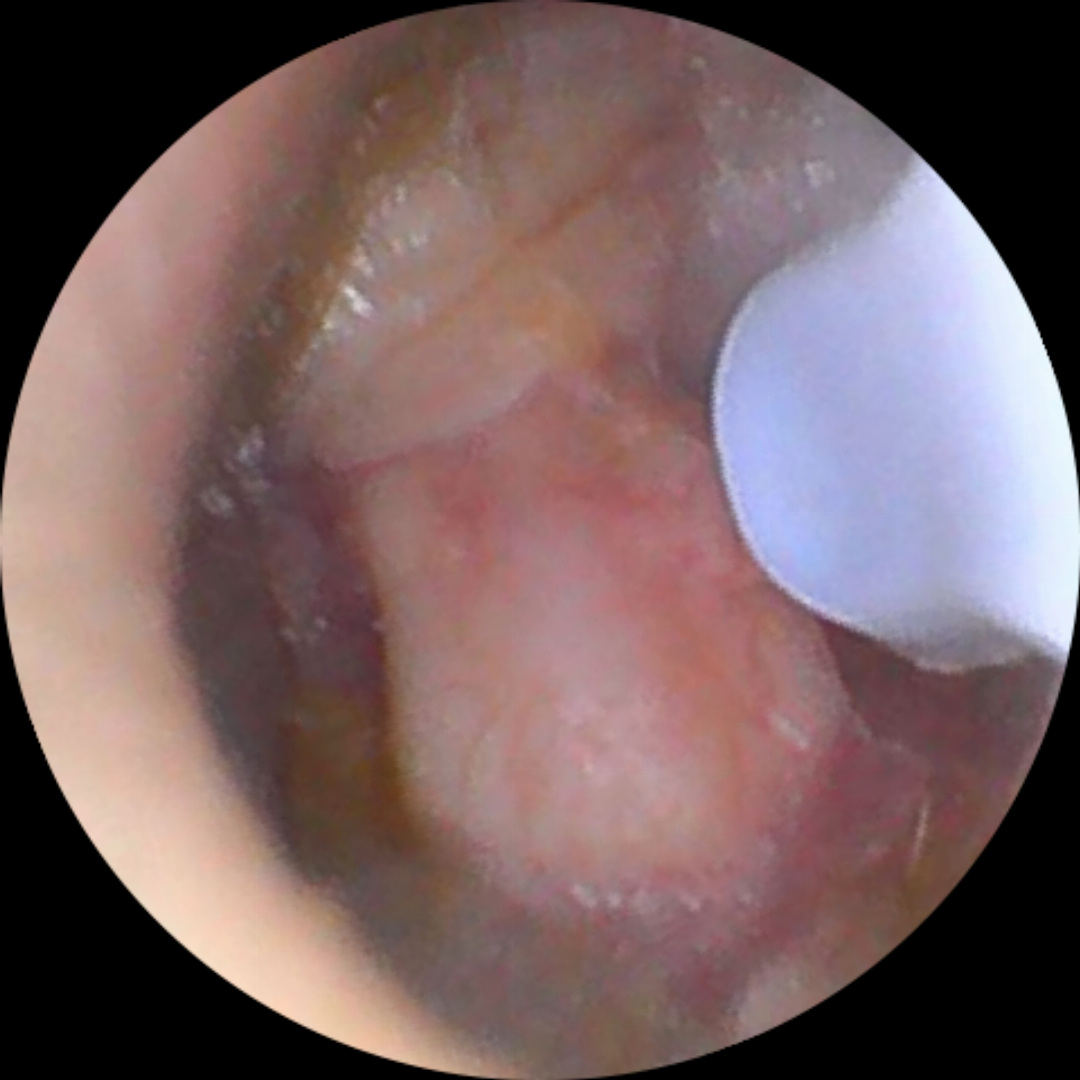

C’est en septembre 2022 que j’ai refait une énorme otite. Plus forte que toutes celles que j’avais connues, elle m’a conduit trois fois aux urgences tant la douleur était insupportable. Après ces multiples passages au CHU, j’ai fini par être examiné par l’ORL en chef du service, également chirurgien, et il a suspecté un cholestéatome. Un scanner a été réalisé la semaine suivante, et le diagnostic est tombé : c’était bel et bien un cholestéatome que je traînais depuis un moment et qui s’infectait, provoquant ces otites atroces.

L’opération a eu lieu, et elle s’est bien passée. J’ai perdu l’enclume et le marteau, car ils étaient trop rongés par la maladie, et une ossiculoplastie a été réalisée avec des cartilages prélevés directement sur mon oreille. Je n’ai eu aucun problème de douleur post-opératoire. Mon audition est revenue petit à petit, sur plusieurs mois, et s’est stabilisée au bout de neuf mois. J’ai perdu les fréquences au-dessus de 8 kHz, ainsi qu’un niveau sonore de -20 dB par rapport à l’oreille gauche. Cependant, le cerveau sait naturellement équilibrer l’audition. J’ai pu continuer à travailler malgré ma déficience, en réorganisant ma manière de travailler et en trouvant des outils de contrôle.

Début 2025, l’ORL m’a fait passer un nouveau scanner. Malheureusement, la maladie a récidivé. Je suis donc repassé sur la table le 30 avril. Le chirurgien en a profité pour affiner le travail sur l’ossiculoplastie et m’a annoncé qu’il y avait une probabilité que mon audition soit de meilleure qualité qu’après la première opération. Je suis actuellement en phase de récupération, et j’ai déjà pas mal retrouvé d’audition au bout d’un mois, contrairement à la première fois où cela avait semblé beaucoup plus long.